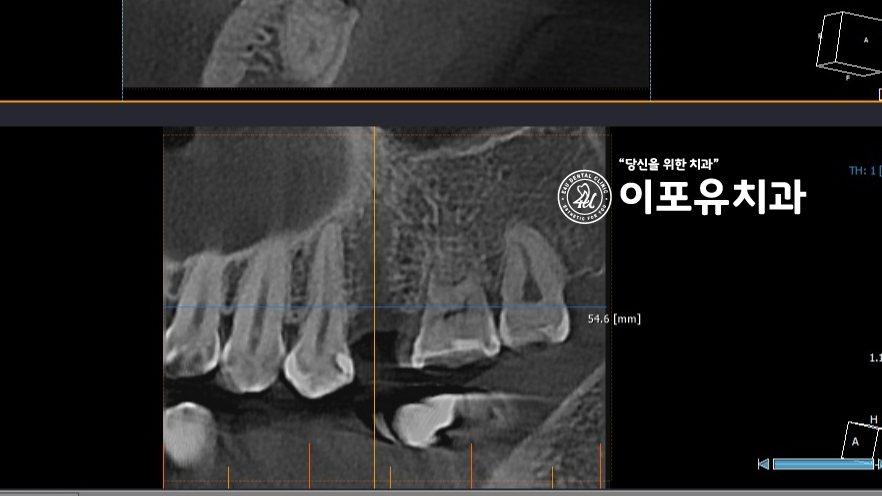

치조골의 양이 충분하지 않았음을

발치 후 촬영한 CT 사진에서 확인할 수 있는데요.

따라서 소량의 골이식을 동반하여

식립을 해야 됩니다.

소구치라 식립 공간이 충분하지 않기에

보다 정확하고 꼼꼼한 판단을 토대로

식립 방향과 각도, 위치를 결정합니다.